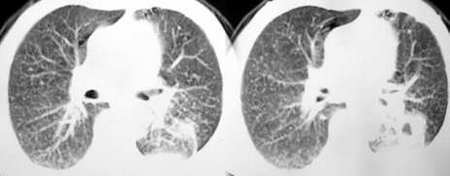

以下是引用sdqzwyx在2005-11-7 19:59:00的发言:[br]双肺弥漫大小不等的粟粒状结节影;肺纹理走行失去自然,粗细不均,边缘不规则,小叶间隔增厚;左上肺示不规则形致密影,从斑块边缘向周围伸出长短不一的致密索条影,临近的血管、支气管和叶间胸膜等结构受牵拉移位;左下肺示不规则团块状影,其内示空洞,洞内壁尚光整,左侧胸腔积液。右肺下叶背段亦示部分病灶融合。双肺可见局限性肺气肿。[br]诊断:结合病史符合三期矽肺表现(少数矽肺纤维斑块内可以形成空洞,一般认为是斑块中央感染引起坏死所致)但尘肺病人易合并肺结核,诊断可为三期+tb。所以此病人应进一步检查是否合并结核。